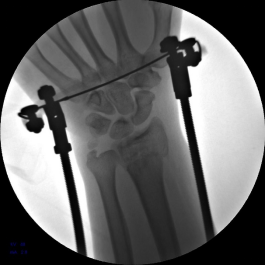

2.安装外固定架,调节螺母纵向牵拉,初步恢复桡骨高度

3.背侧穿针撬拨,继续恢复桡骨高度